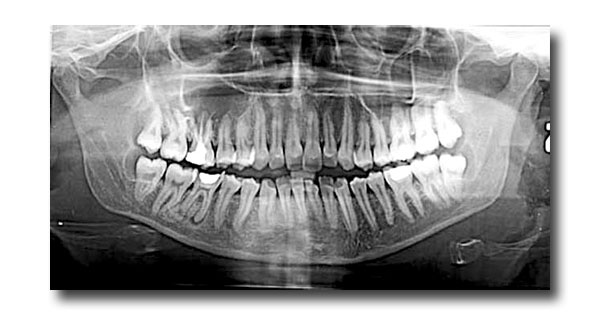

La Radiografia Panoramica Dentale è un esame a scopo diagnostico delle due arcate dentali complete e del distretto maxillo-facciale.

Viene effettuata per avere una visione globale dello stato dei denti, dell’osso mandibolare e mascellare, delle articolazioni e dei tessuti gengivali.

Questo esame consente di visualizzare con una sola esposizione tutte le zone oggetto del quesito diagnostico, offrendo all’odontoiatra una visuale completa dell’anatomia del paziente.L'apparecchiatura a nostra disposizione consente di acquisire anche solo una parte delle strutture mascellari, riducendo se il caso, la dose radiogena, quando è necessario indagare solo una parte delle strutture stesse.